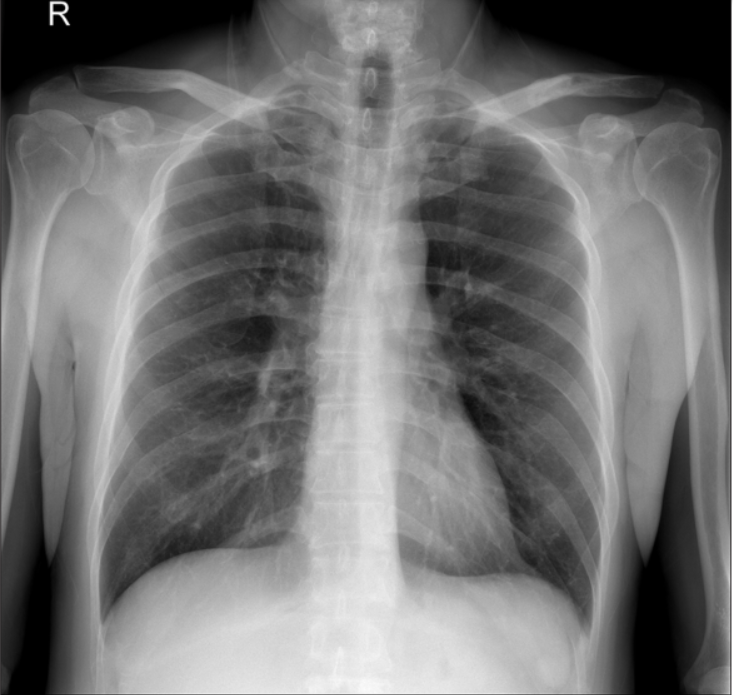

急诊就诊3天后门诊随访x线片显示锁骨中轴骨折倒v型移位